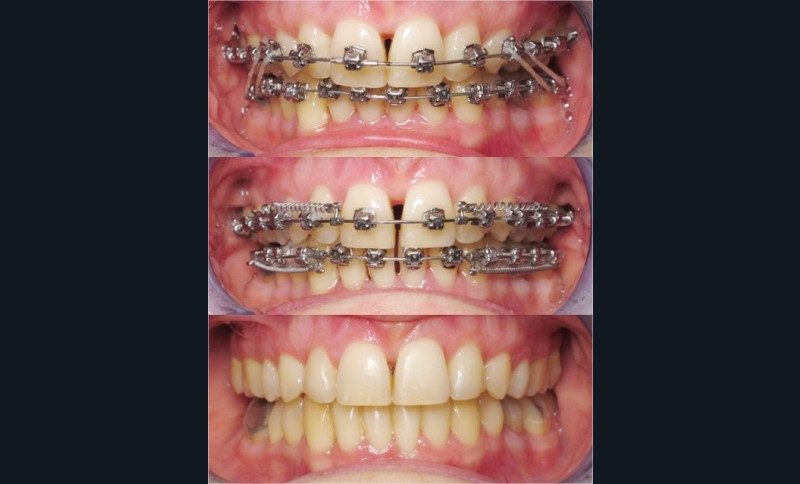

Un appareillage Damon métal a été mis en place, réalisé à partir d’un set up numérique Insignia pour obtenir un contrôle précis des torques et de la forme d’arcade et réduire le temps de finition grâce à un collage indirect très précis.

De larges surélévations postérieures étalées ont été mises en place et la patiente a porté des élastiques précoces suivant les principes de la technique Damon. Les 14 et 24 rempliront le rôle des 13 et 23.

L’objectif, en utilisant la technique Insignia est de réduire le temps de traitement de 28 à 18 mois avec 12 rendez-vous (fig. 5 à 14).

Les objectifs de traitement ont été remplis. Nous avons observé un excellent contrôle du torque et une absence de perte de l’occlusion postérieure grâce à la technique Insignia.